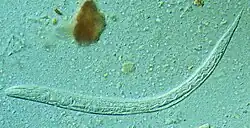

| First stage larva (L1) of S. stercoralis | |

Whereas males grow to only about 0.9 mm (0.04 in) in length, females can grow from 2.0 to 2.5 mm (0.08 to 0.10 in). Both sexes also possess a tiny buccal capsule and cylindrical esophagus without a posterior bulb.[7] In the free-living stage, the esophagi of both sexes are rhabditiform. Males can be distinguished from females by two structures: the spicules and gubernaculum.